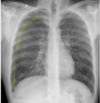

What is highlighted?

Lingula

102

**Answer: Chronic Obstructive Pulmonary Disease** ## Footnote In normal subjects, the diaphragm is intersected by the 5th to 7th anterior ribs in the mid-clavicular line - in this patient you can count up to 9 ribs before reaching the diaphragm → hyperexpanded lungs. Flattening of the diaphragm is also observed in this x-ray which is a reliable feature of lung hyperexpansion.